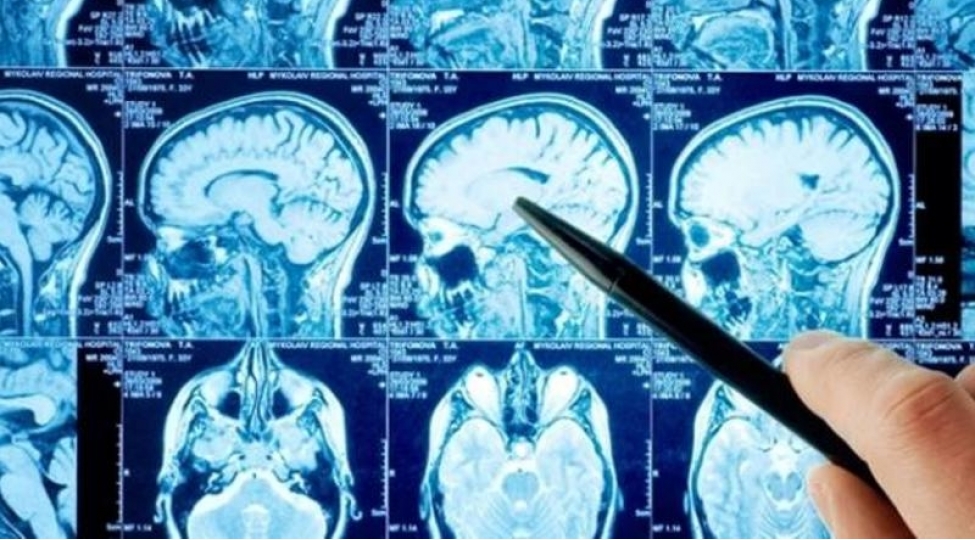

60 il beyni olmadan SAĞLAM YAŞADI

Moskvada xəstəxanaların birində həkimlər beyninin yarısı olmadan 60 il ömür sürən xəstə müəyyən edib.

Publika.az Rusiya mətbuatına istinadən xəbər verir ki, xəstənin vücud funksiyalarında heç bir qüsurun olmaması həkimlərin böyük təəccübünə səbəb olub. Qeyri-adi kliniki hal qarşısında təəccüblərini gizlətməyən həkimlər 60 yaşlı təqaüdçü mühəndisin bütün bədən funksiyalarının normal çalışdığını qeyd edib.

Anikina 60 yaşlı xəstənin indiyə qədər beyninin yarısının olmadığını bilmədən yaşadığını qeyd edib.